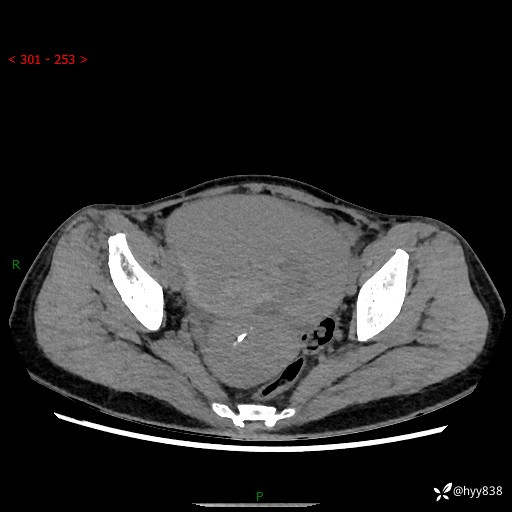

【患者信息】:女,50岁

【主诉】:外院超声发现腹盆肿块,为进一步诊治来我院,门诊已“盆腔肿块”收入院。

腹盆CT平扫+增强

【临床诊断】:盆腔肿瘤